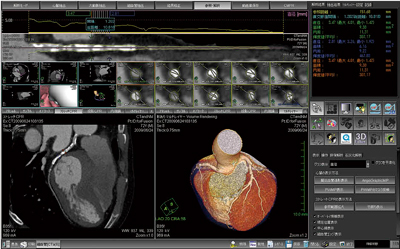

2.新ビューワ

ネットワーク型ワークステーションの普及に伴い,以前よりワークステーション側に読影機能の充実を求める声もあった。今回のAZE VirtualPlaceでは,3D解析機能の向上だけでなく,これらの声を取り入れて読影機能の大幅な向上を図ることに成功した。

新ビューワの特長としては,患者リスト選択から瞬時にビューワ表示が可能で,同一Studyのサムネイルを一覧表示できることや,他患者への瞬時の切り替えが可能となった点である。また,サムネイルから直接Drag&Dropでビューワ表示可能で,スピーディでインタラクティブな読影環境を提供する。これに加え,決まったレイアウトと決まった撮影条件の画像を自動配置設定が可能となっており,ルーチン作業のさらなる効率化を図ることができる(図4)。

図4 新ビューワ画面